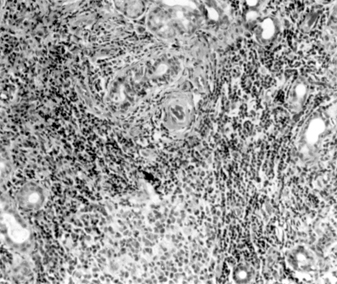

The diagnosis is confirmed by demonstrating lymphocytic and plasma cell infiltration of the accessory salivary glands in a labial biopsy obtained by means of a simple surgical procedure (Figure 5-15).

Figure 5-15

Figure 5-15: Mononuclear infiltration of the accessory salivary glands of a patient with Sjögren's syndrome. (Courtesy of K Tabbara.)